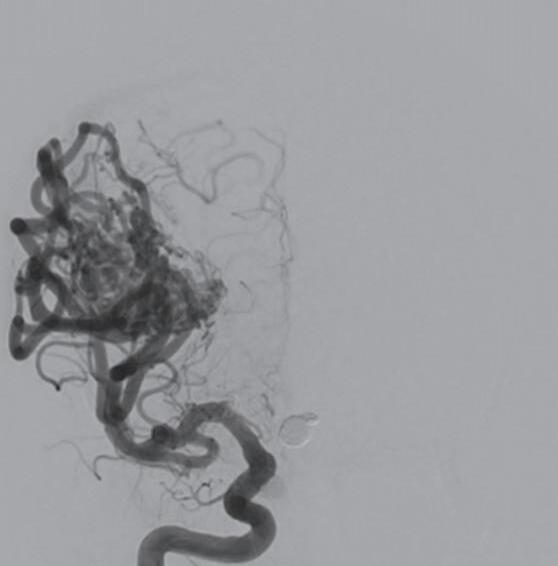

Fig. 1-8. (a-c) RNM T1 com contraste, cortes sagital (a), coronal (b) e axial (c) demonstrando MAV não rota com nidus localizado no lobo occipital à esquerda (setas longas). (d) Arteriografia digital cerebral com injeção de contraste via carótida direita (AP) mostrando a contribuição da carótida direita na irrigação da MAV contralateral. (e,f) Com injeção de contraste via carótida esquerda, em Perfil e AP respectivamente, observa-se nidus compacto nutrido por ramos da artéria cerebral média à esquerda e a veia de drenagem precoce se dirigindo para o seio sagital superior. Projeções em AP (g) e em perfil (h) demonstrando a contribuição do sistema vertebrobasilar por meio de ramos distais da artéria cerebral posterior à esquerda e drenagem para os seios sagital superior e sigmoide à esquerda (setas curtas).